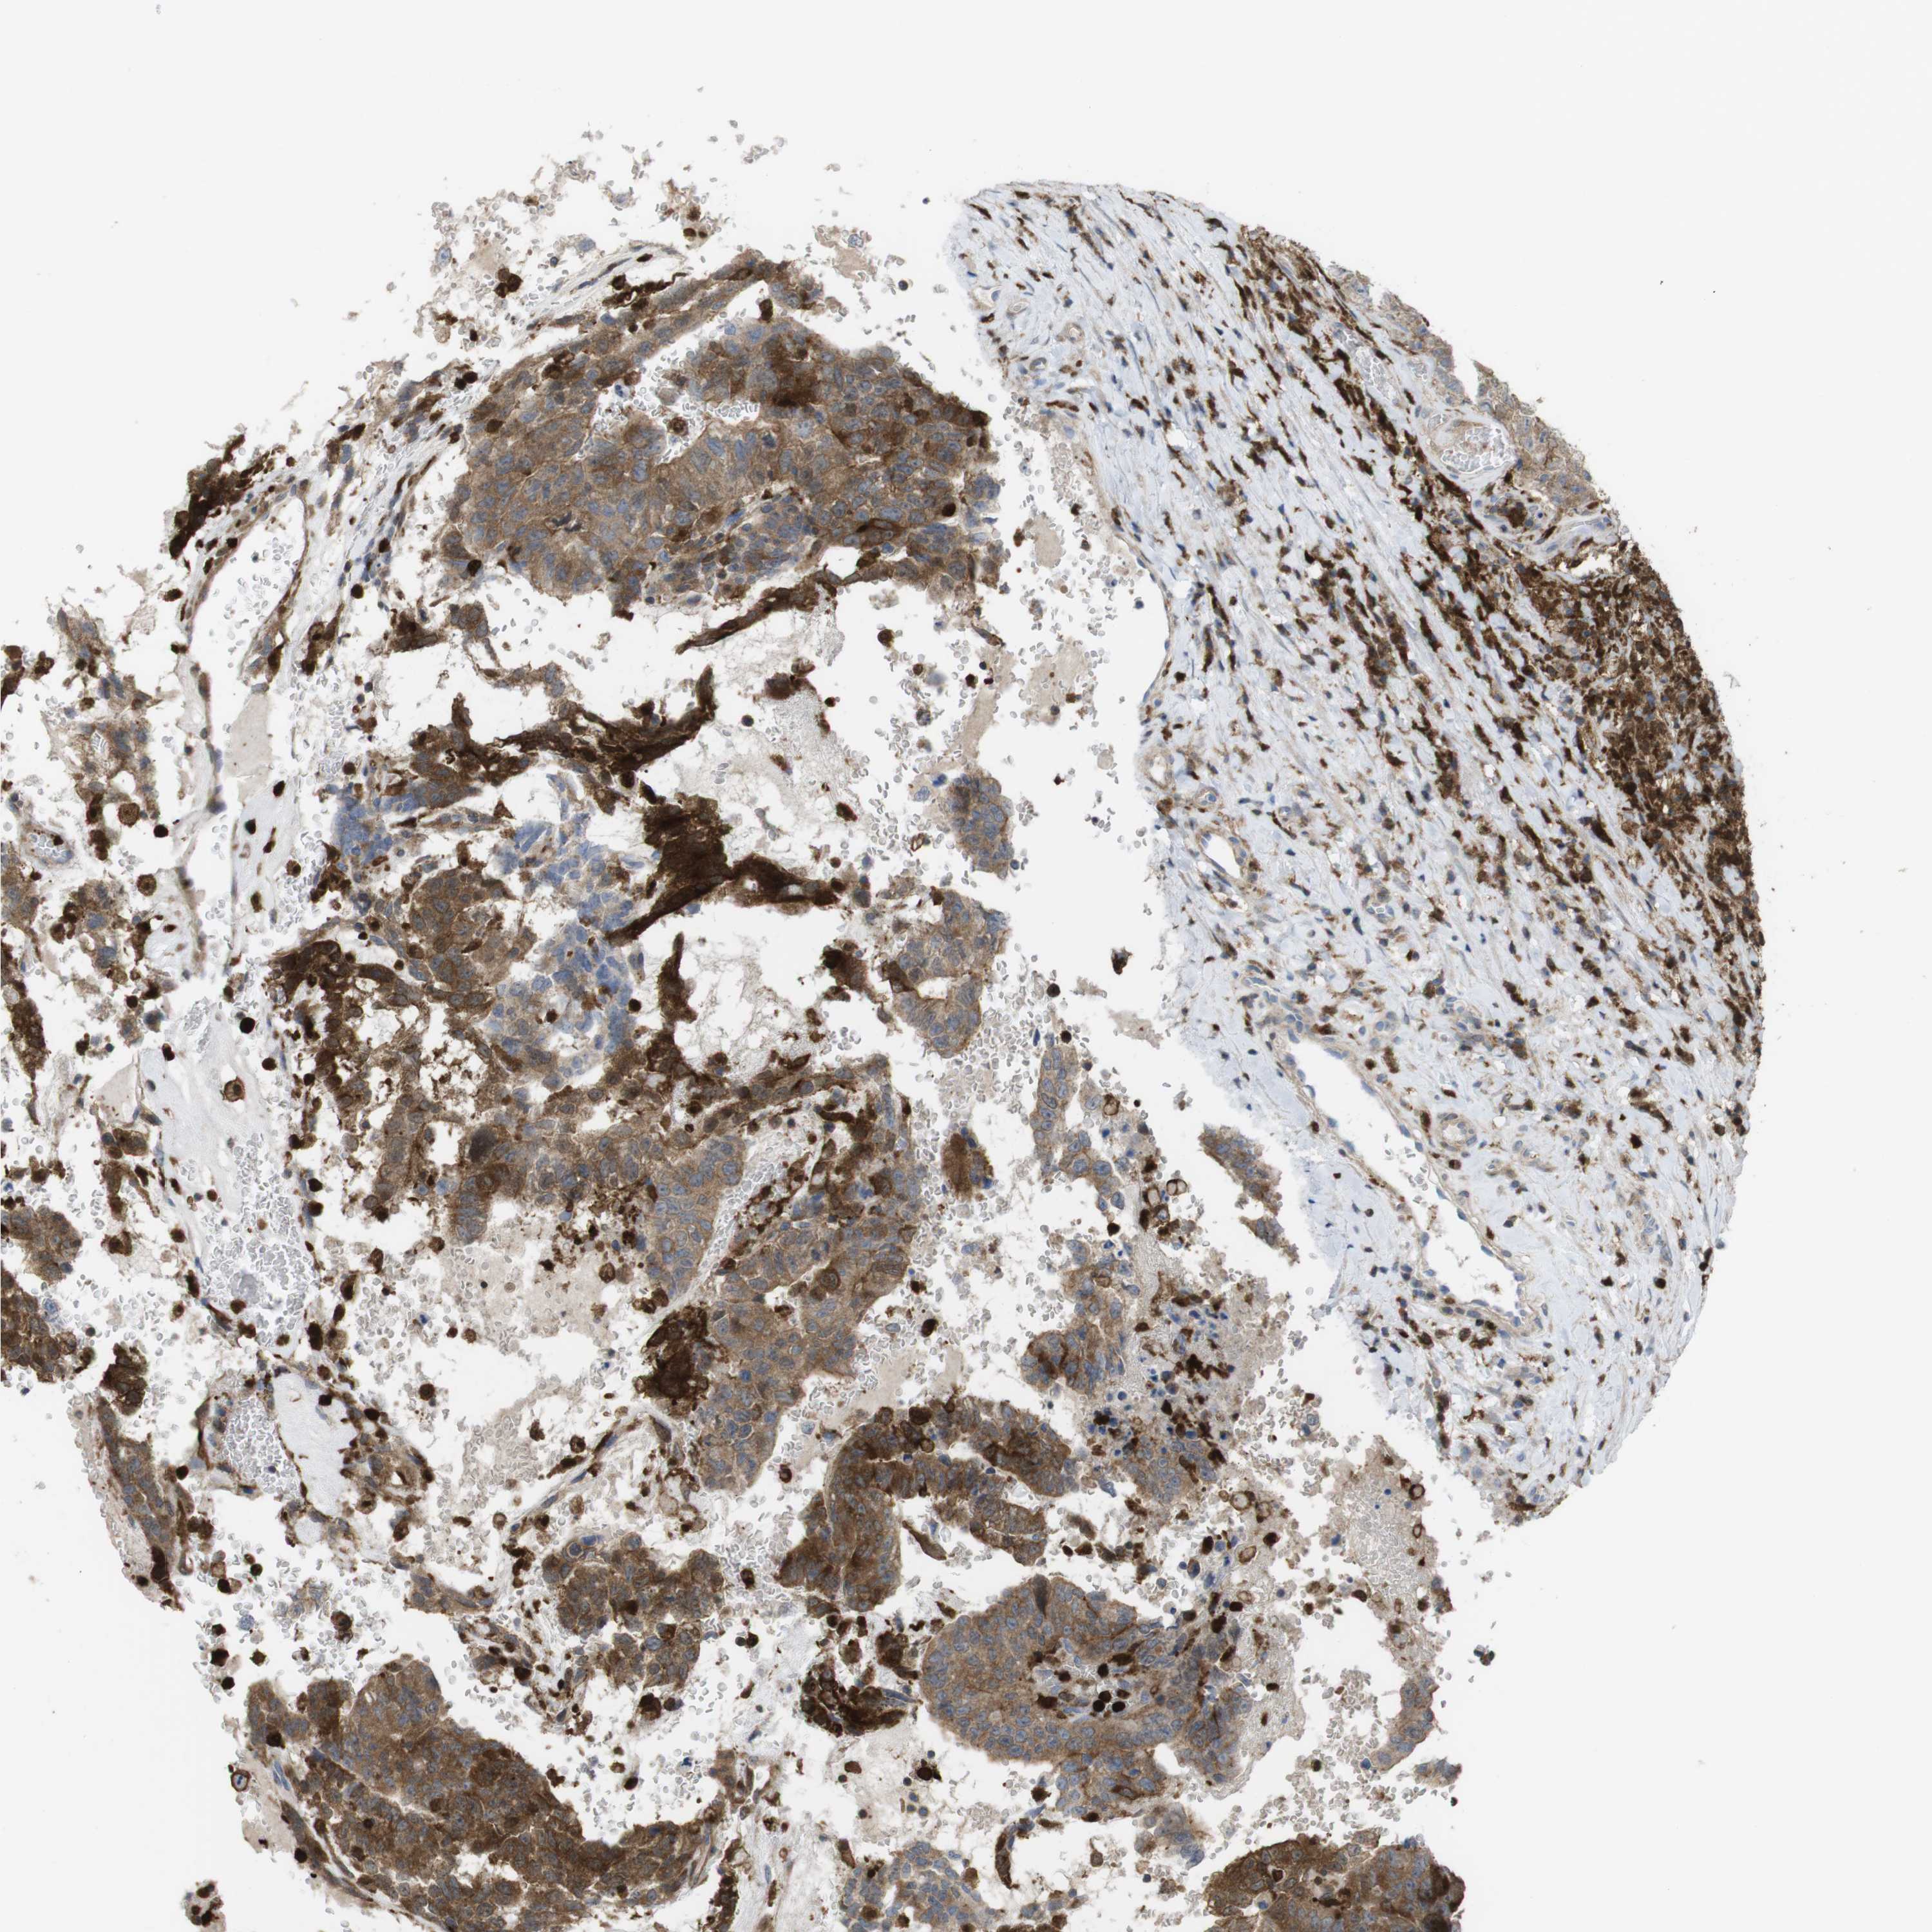

TESTIS CANCER - Protein expressioni

A mouse-over function shows sample information and annotation data. Click on an image to view it in a full screen mode. Samples can be filtered based on level of antibody staining by selecting one or several of the following categories: high, medium, low and not detected. The assay and annotation is described here.

Note that samples used for immunohistochemistry by the Human Protein Atlas do not correspond to samples in the TCGA dataset.

Antibody stainingi

Antibody staining in the annotated cell types in the current human tissue is reported as not detected, low, medium, or high, based on conventional immunohistochemistry profiling in selected tissues. This score is based on the combination of the staining intensity and fraction of stained cells.

Each image is clickable and will lead to virtual microscopy that enables deeper exploration of all samples and also displays staining intensity scores, fraction scores and subcellular localization as well as patient and tissue information for each sample.

Antibody HPA001890

Antibody CAB010469

Antibody CAB013225

Carcinoma, Embryonal, NOS

Seminoma, NOS